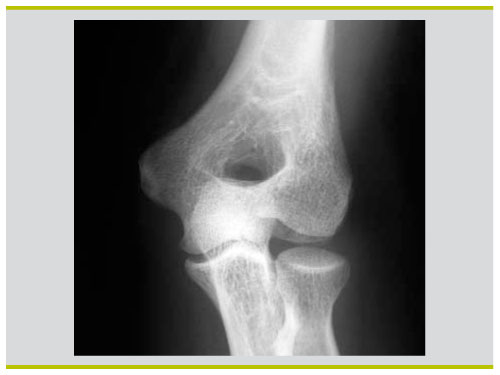

Il est important de différencier la contusion du coude, en particulier la blessure au coude chez l'enfant, des entorses, des dislocations et des fractures L'enfant est très clairement vu limiter les mouvements de flexionextension, le bras souvent blessé, il essaie de maintenir sa main, en plus d'un œdème osseux de coude cassé est. Fracture pilon tibial Fracture bimaléollaire avec luxation Fracture de la cheville Fracture tête radiale coude droit avec prothèse inerte Fracture du lifranc avec fracture déplacée du premier cunéiforme Marcher correctement apres fracture Tibia/Peroné Plus de sujets relatifs à. L’entorse légère Douleur immédiate, qui peut disparaître rapidement mais revenir de manière lancinante au bout de quelques heures Les mouvements sont possibles;.

Un traumatisme isolé du coude doit faire rechercher une lésion associée à l’épaule, au bras, à l’avantbras et au poignet a) ostéoarticulaire b) vasculonerveuse Le coude doit être mobilisé précocement à cause du risque de raideur posttraumatique ou postopératoire 21 Luxation du coude. > au développement d’une l’arthropathie acromioclaviculaire Traitement chirurgical des entorses acromioclaviculaires de stade 4 et 5 Dans les stades 4 et 5 les l’ensemble des attaches ligamentaires sont rompues et entraîne une perte de contact entre acromion et clavicule. • au pli du coude (tendinite du biceps) • à l’arrière du coude (tendinite du triceps) Pour soigner une tendinite du coude, il faut appliquer les remèdes naturels suivants 1) Mettre au repos le coude et le poignet Pour commencer, vous devez arrêter toutes les activités augmentant la douleur.

Examen clinique du coude pour entorse du ligament latéral interne https//wwwsportsanteconseilorg/support/helpus. L'entorse est un étirement ou une déchirure d'un ou de plusieurs ligaments d'une articulation Les principaux symptômes d'une entorse sont la douleur et l'inflammation locale puis un oedème, des spasmes peuvent aussi intervenir Dans tous les cas, c'est le froid qui est recommandé, il ne faut pas mettre de chaleur ni masser Mettez votre articulation et vos muscles alentour au repos et. Conduite à tenir (2) • Si le coude ne se reluxe pas en extension – Stabilité au testing • Attelle en flexion 90° pendant quelques jours puis rééducation – Instabilité au testing • Orthèse articulée maintenant l’avantbras en pronation • Si le coude se reluxe en extension – Immobilisation trois semaines en flexion.

Entorse au coude Avezvous une douleur au coude suite à un accident soit un coup ou une torsion La douleur peut être à l’intérieur, à l’extérieur ou diffuse au niveau du coude. L’entorse du coude est la lésion des ligaments situées entre l’humérus et l’ulna (cubitus) au niveau du coude ou entre le radius et l’ulna (cubitus) Si l’entorse est importante, cela peut aboutir à la luxation du coude Comment apparaît une entorse du ligament collatéral médial du coude?. Les tendinites au coude ne touchent pas que les sportifs mais peuvent également survenir chez les personnes effectuant des mouvements répétitifs (menuisiers, maçons, jardiniers, etc) En effet, une sollicitation excessive des tendons entraîne des microt.